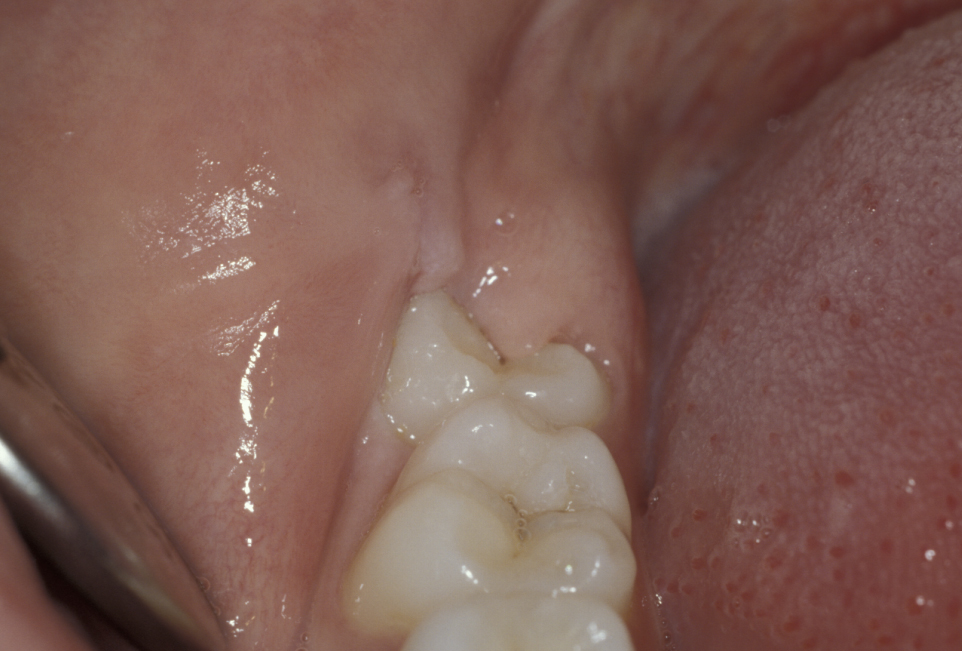

The commonest indication is recurrent pericoronitis. Pericoronitis is inflammation and infection of the mucosal flap (operculum) overlying a partially erupted tooth, usually the lower third molar (Figure 1). Pericoronitis may be acute or chronic.

Figure 2 and Figure 3 illustrate examples of indications for removal of a third molar tooth.